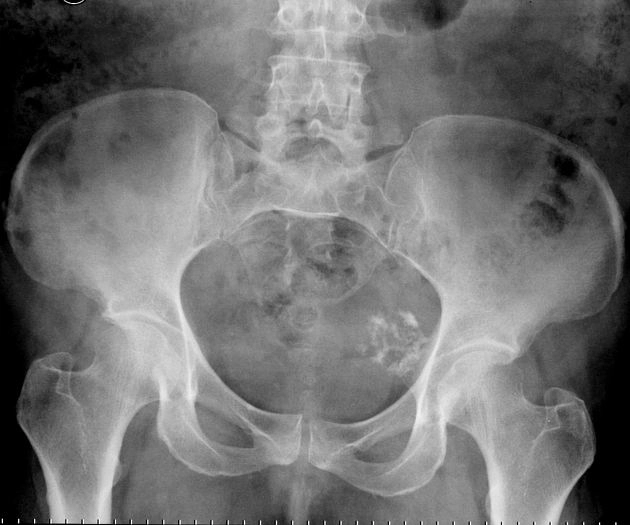

Tiếp cận X- quang xương chậu